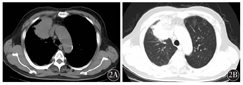

例2,男性,46岁,因低热2个月余,发现肺占位3 d于2013年3月1日入院。患者入院前间断发热2个月,体温最高38.5℃,伴咳嗽、咳白痰,给予抗生素治疗后好转。逐渐出现胸闷,活动后加重,在外院行CT检查发现右肺中叶占位,不排除周围型肺癌,右侧胸腔少量积液。以右肺占位待查收入院,查体:一般情况好,全身皮肤黏膜无黄染及皮下出血点,浅表淋巴结未触及,左肺呼吸音清,右肺呼吸音低,心率90次/min,律齐,各瓣膜听诊区无杂音。肝脾肋缘下未触及。入院后实验室检查,血常规:WBC 16.57× 109/L,Hb 123 g/L,Plt 408×109/L,LDH 291 U/L,血β2微球蛋白3 mg/L,清蛋白36 g/L。颈胸腹盆CT示:右肺上叶前段肿块,心包及双侧胸腔积液,右侧睾丸鞘膜腔积液(图2)。骨髓穿刺示增生活跃,行支气管镜检查未见异常。CT引导下肺穿刺发现炎性细胞,病理淋巴瘤不能排除,免疫组织化学:CK+、Vim+/-、CK7+、TTF-1+、CK5/6-、Syn-、CD56-,SCLC-、LCA+ ,Ki-67+、CD5+、CD4+、EMA-、CD30-、CD2点阳性、CD3+、CD79a-、ALK-、TdT-、CD43灶阳性,提示:右肺非特异性T细胞性非霍奇金淋巴瘤。行CHOP方案(环磷酰胺+多柔比星+长春新碱+泼尼松)化疗6个疗程,病灶较前缩小,达到部分缓解(PR)。2013年7月24日行右肺病灶处6 MV X线放疗,剂量45 Gy/25次。之后定期复查,病灶稳定,未见复发,生存中。

2A:纵隔窗,右肺上叶前段肿块,心包及双侧胸腔积液;2B:肺窗,右肺上叶前段不规则肿块